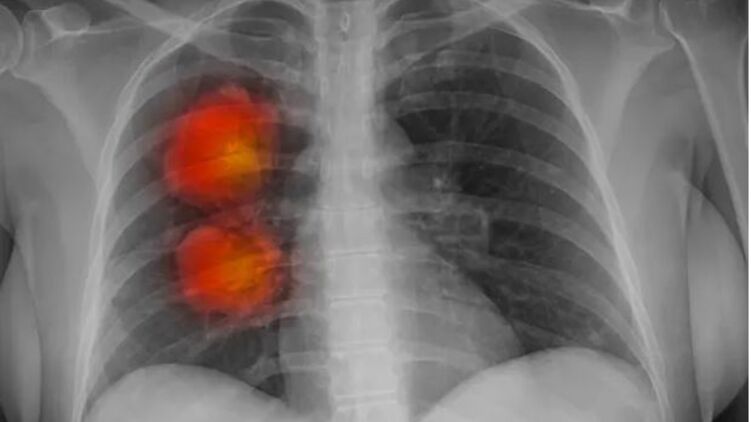

Инструмент искусственного интеллекта был разработан экспертами фонда Royal Marsden NHS, Института исследования рака в Лондоне и Имперского колледжа Лондона. Он может определить, являются ли аномальные новообразования, обнаруженные на КТ, злокачественными.

Команда использовала компьютерную томографию около 500 пациентов с большими узлами в легких для разработки алгоритма искусственного интеллекта. Этот метод может извлекать жизненно важную информацию из медицинских изображений, которые трудно заметить человеческому глазу.

Согласно первоначальным результатам, модель ИИ, по-видимому, точно идентифицирует раковые крупные узелки в легких.